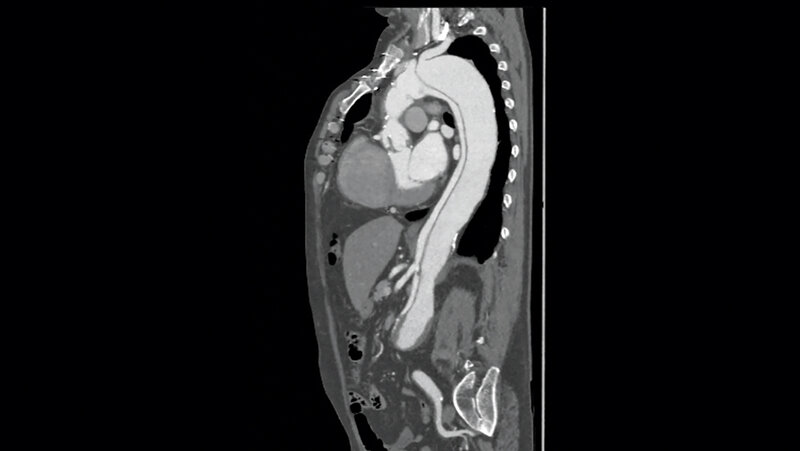

Die Falldarstellung zeigt den Erkrankungsverlauf eines 49-jährigen Patienten mit Typ-B-Aortendissektion. Relevante Vorerkrankungen und Risikofaktoren sind eine arterielle Hypertonie sowie eine Übergewichtigkeit und ein Nikotinabusus.

Schlüsselwörter: Aortendissektion, Typ-B-Aortendissektion, CT, Aortenstentprothese